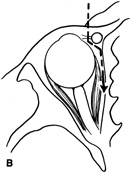

Valuable information about the nature and extent of an orbital pathologic process is provided by imaging studies such as computed tomography (CT) scan, magnetic resonance imaging (MRI), and orbital echography. Better spatial resolution, ready accessibility, and lower cost make CT the preferred choice for orbital imaging in most cases. Orbital fat provides a natural contrast between most adjacent orbital structures on CT scanning, and orbital bones are visualized well. Computed tomography is essential for evaluation of the orbital bones because they cannot be imaged with MRI. Direct coronal or sagittal images are important to identify the relationship of a lesion to the optic nerve so that the surgical approach can be planned to avoid traversing the optic nerve (Fig. 1).

Fig. 1. A. Axial CT scan demonstrating a large, well-encapsulated lesion in the orbital apex. Coronal (B) and sagittal (C) scans demonstrate that the mass lies inferior and medial to the optic nerve within the intraconal space. This information is useful in planning the surgical approach to the mass, which should avoid traversing the optic nerve.